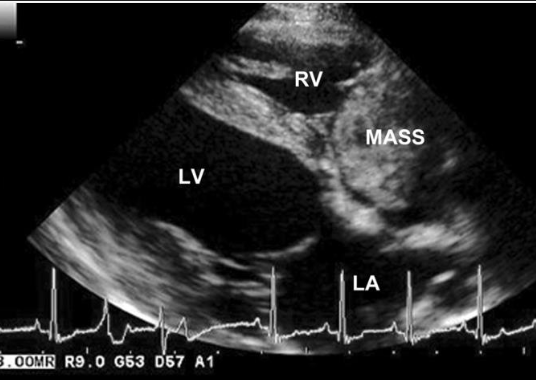

how can echocardiogram be used to diagnose hemangiosarcoma?

-to identify mass in right atrium or appendage

-pericardial effusion improves detection of mass (SP=100%, SN=82%)